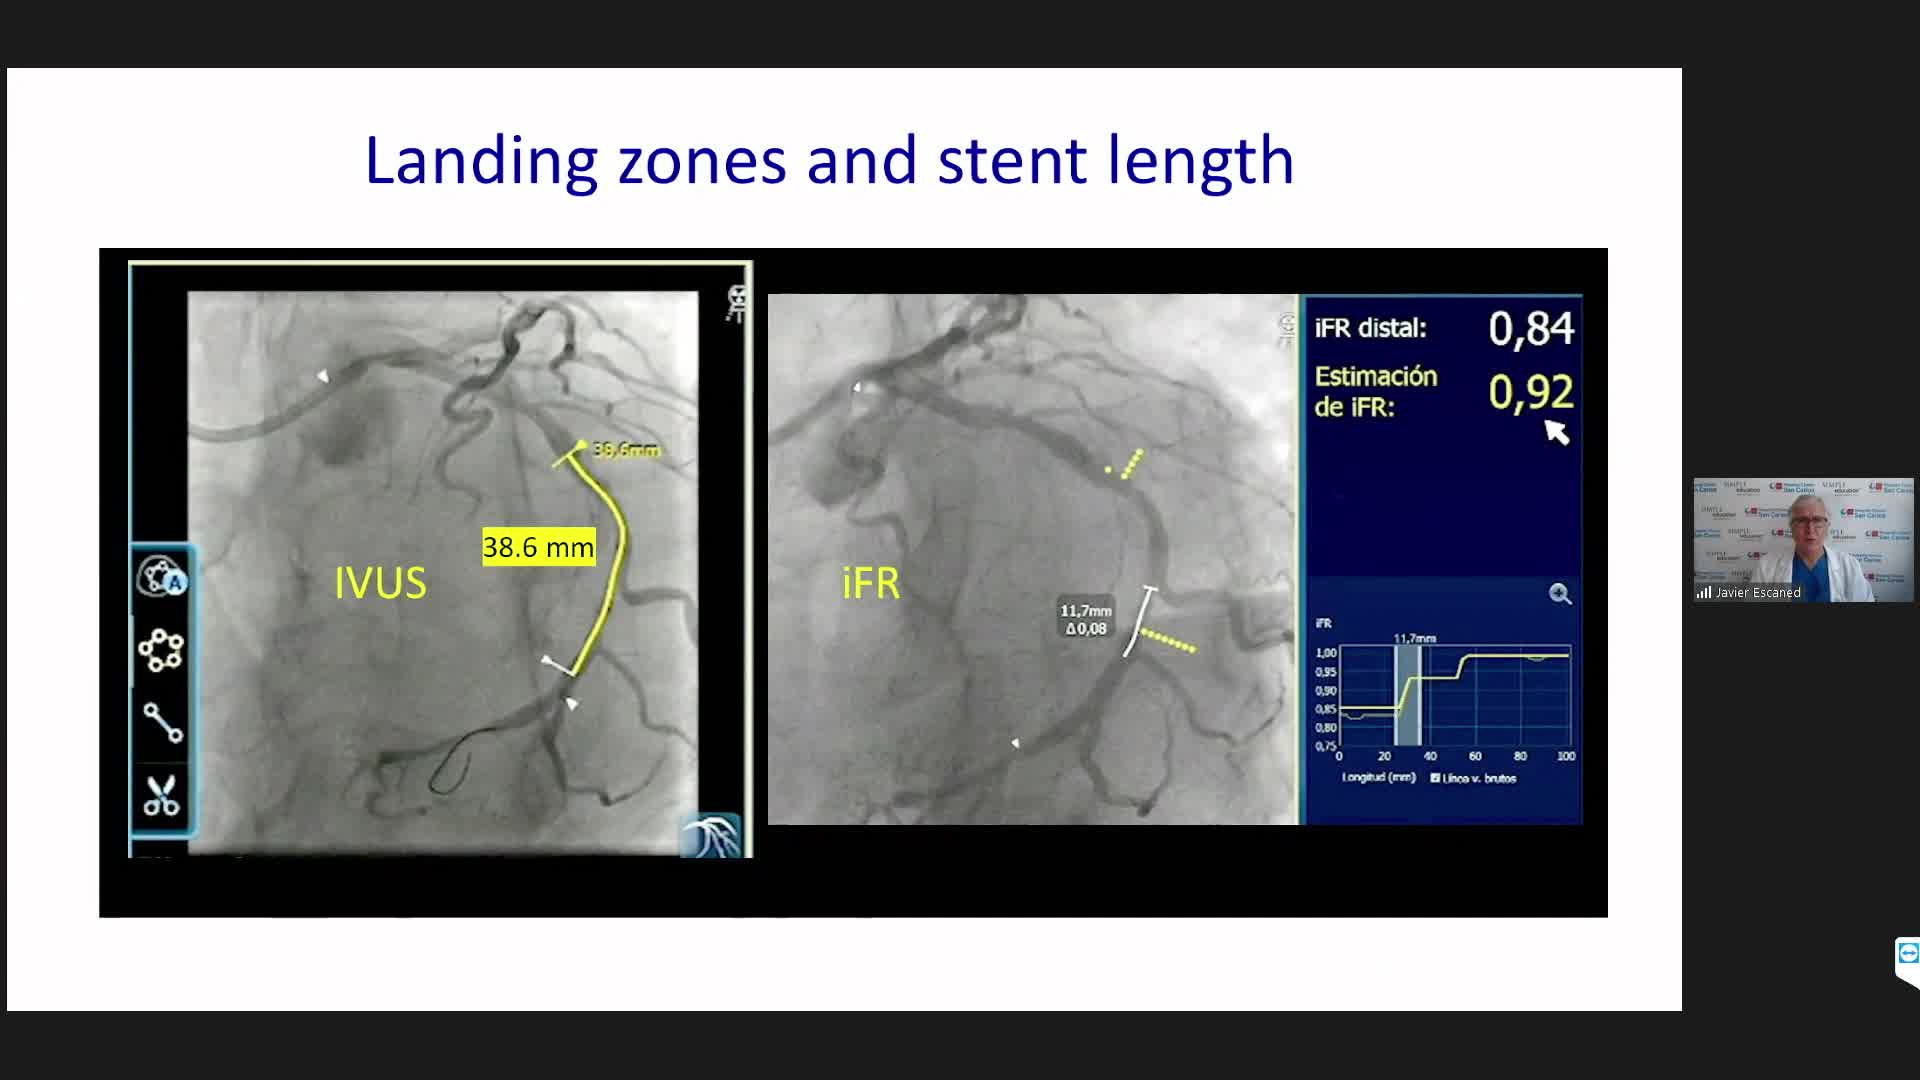

Best practices and personalised medicine in complex PCI - Prof Javier Escaned

Essential steps for physiology-based PCI planning and guidance - Dr Allen Jeremias

Coronary Bifurcations: An Update on Diagnosis, PCI planning and Imaging and PhysiologyGuidance - Dr Dejan Milasinovic